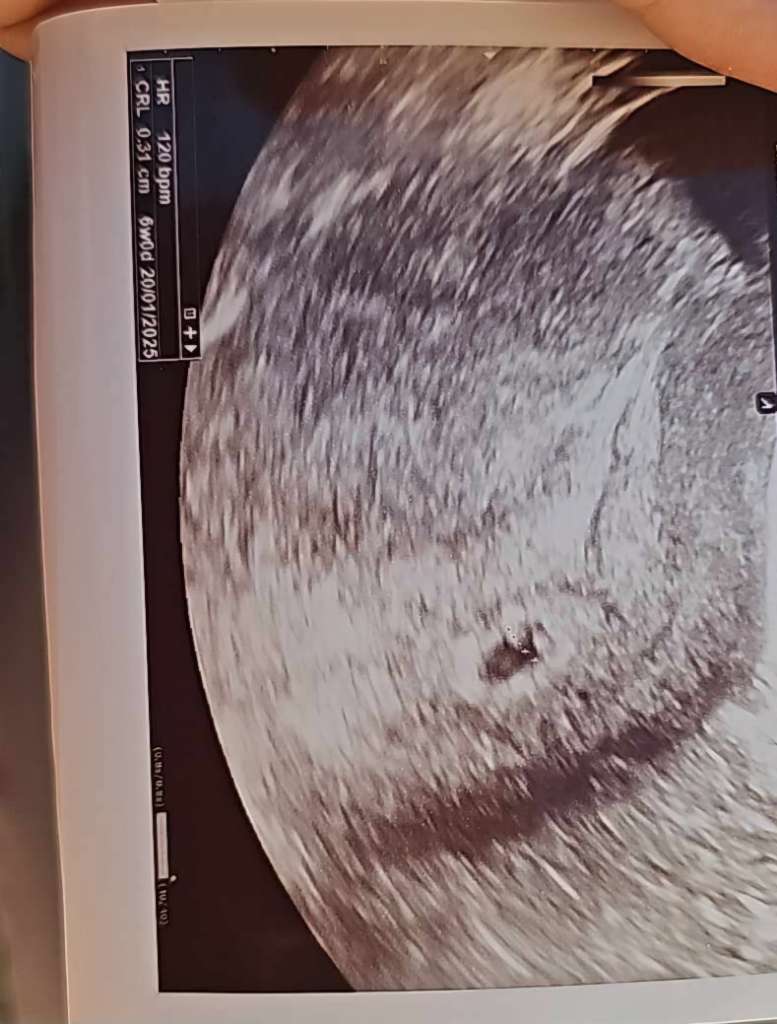

Też mam takie myśli ale pociesza mnie, że maluch jest w USG adekwatny do wieku 🙂 wtedy już na pierwszym USG była różnica 5 dni. Tak jakby zarodek się zatrzymał. To było USG po potwierdzonym terminie owulacji ....realnie gdybym wtedy powiedziała lekarzowi, że jestem po monitoringu to pewnie wiedziałabym odrazu, że poronie 🤷

• 4a05058e-3ae4-4c78-ab3f-403e4bab2da5.jpeg

72,6 KB · Wyświetleń: 107